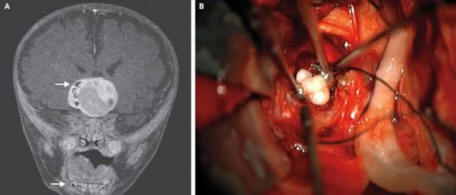

4. A csecsemő agyában ritka daganat kiderült, hogy fog

fénykép nyílt forrásokból

Előfordulhat, hogy a Maryland 4 hónapos kisbabája első olyan személy, akinek daganata volt az agyában, amely fogassá vált. Először az orvosok azt gyanították, hogy valami nincs rendben, amikor a gyermek feje látszik gyorsabban növekszik, mint korának gyermekeire jellemző.

Az agyszkennelés kimutatta a daganatot általában az emberi fogakra emlékeztető struktúrák, általában megtalálhatók az alsó állkapocsban. A daganat eltávolították, és a fiú érezte magát jól magad.